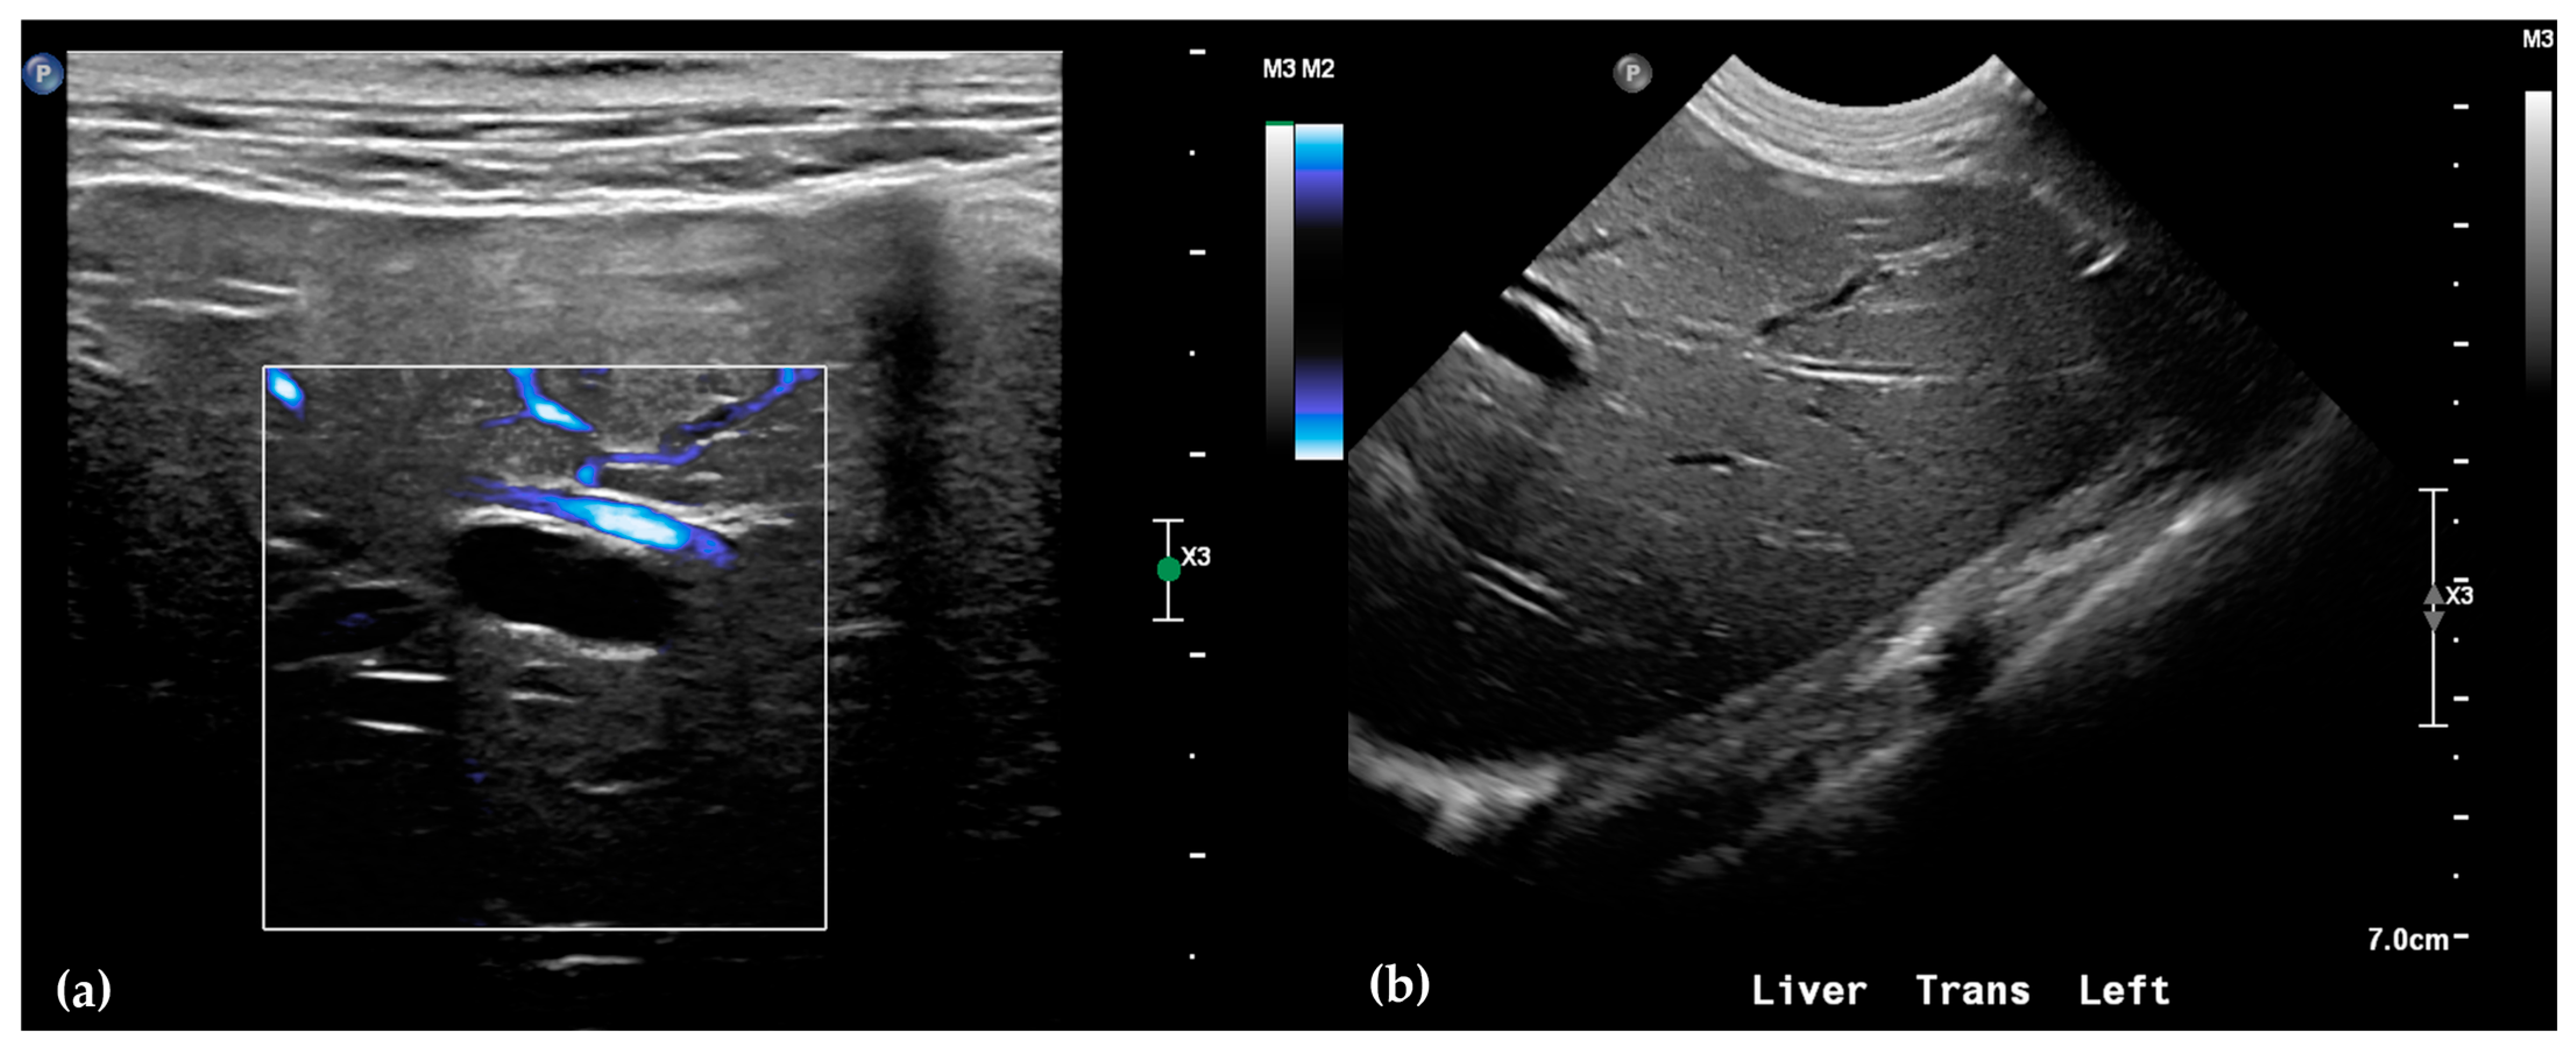

Abdominal radiographs showed no significant abnormalities except a large amount of fecal material in the large intestine. The patient was placed in dorsal recumbency for an abdominal ultrasound (microconvex and linear probes 12–18 MHz, Epiq 5G, Philips Ultrasound, Bothell, WA, USA), with the ventrum shaved from above the xiphoid to the pubis in a roughly square-shaped region. Ultrasound coupling gel and alcohol were used for image optimization. The gallbladder was moderately filled with anechoic fluid and the cystic duct appropriately tapered to the common bile duct (CBD). The CBD could not be traced in its entirety, but the more distal identified segments were multifocally dilated, measuring up to 0.6 cm in diameter (outer wall to outer wall; Figure 1a). At its distal-most aspect, as it approached the duodenal papilla, the CBD abruptly tapered without a discrete intraluminal or extraluminal cause (Figure 1b). Several intrahepatic biliary ducts within the left liver hemisphere were distended distally, measuring up to 0.5 cm in dilation (inner wall to inner wall; Figure 2a,b). No intrahepatic biliary duct dilation of the right hepatic hemisphere was noted. Due to a concern for an unidentified biliary duct obstruction contributing to the patient’s clinical signs/changes, a dual phase contrast abdominal computed tomographic (CT) study was pursued for further evaluation.

Figure 1.

Ultrasound images of the liver. A portion of the common bile duct (CBD) is moderately-markedly distended (between + calipers) (a). Ultrasound image of the duodenum (black-rimmed white star), common bile duct (white arrowhead), and pancreas (blue-rimmed white circle). The distal common bile duct at the level of the duodenal papilla with abrupt narrowing (between calipers) (b).

Figure 2.

Ultrasound of the left liver. Power Doppler, within white box, of the left liver demonstrating slow flow (blue) through adjacent hepatic vasculature and no flow (black) within the anechoic structure, consistent with a dilated intrahepatic biliary duct (a). Several anechoic tubular structures without peripheral hyperechoic walls, consistent with peripheral intrahepatic biliary duct dilation (b).